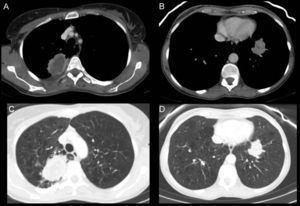

(A and C) Axial CT slices in the mediastinal and lung windows, respectively. A solid mass 6cm×4cm with infiltrative margins, containing necrosis, and peripheral enhancement in the posterior segment of the RUL adjacent to the posterior pleura. (B and D) Axial CT slices in the mediastinal and lung windows. Another solid lesion is seen in the LLL, adjacent to the diaphragmatic pleura, with infiltrative contours and less necrosis. (E and F) Axial CT slices in lung window, 6 months after starting bevacizumab treatment. In E, the RUL lesion can be seen to be larger, cavitated and with no solid component, and in F, the solid tumor in the LLL is smaller with lower attenuation than in images B and D.

In the follow-up CT, the RUL lesion had increased in size, with cavitation and reduced solid component (Fig. 1E). The LLL tumor and lymphadenopathy had reduced in size and attenuation (Fig. 1F).

There have been far-reaching changes in the treatment of advanced lung cancer, with the introduction of molecular targets, and immunological and antiangiogenic therapy that have different mechanisms of action and patterns of response from those of conventional chemotherapy. The effects of antiangiogenics include not only change in size, but also the appearance of cavitation (20%), considered a criterion for good treatment response. Although the overall size of the lesions increases, cavitation and reduced solid component are considered a positive response.1